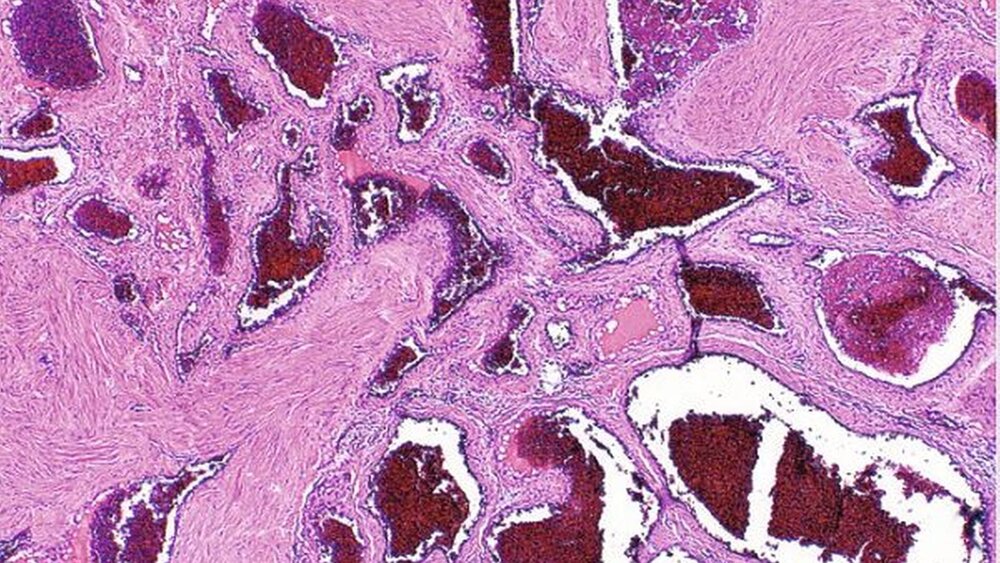

Die Entfernung des Befundes erfolgte in Intubationsnarkose von intraoral über eine marginale Inzision im Bereich des linken Oberkiefers. Intraoperativ stellte sich der Tumor als bekapseltes Gefäßkonvolut dar, so dass hieraus die klinische Diagnose einer vaskulären Malformation zu stellen war. Der Tumor ließ sich aus dem lockeren retromaxillären Gewebe mobilisieren und in toto unter Ligatur des dorsalen Gefäßstiels entwickeln (Abbildung 3). Im Anschnitt (Abbildung 4 ), nach dem Exprimieren und Abspülen des Blutes, zeigt sich das maschenartige Gebilde aus zahlreichen lakunären Gefäß-Räumen unterschiedlicher Kaliber und damit ein typisches Bild einer vaskulären Malformation.

Histologisch bestätigte sich diese Diagnose anhand eines schwammartigen Aufbaus aus großen sinusoidalen Bluträumen mit endothelialer Auskleidung ohne atypische oder proliferierende Zellen. Eine weiterführende Therapie war damit nicht erforderlich.